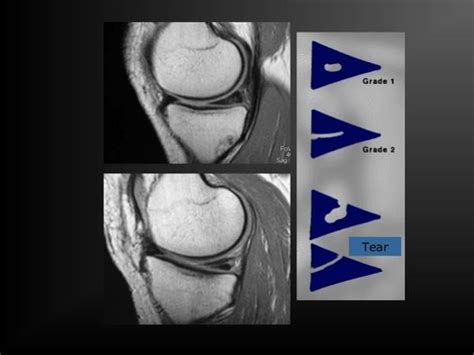

半月板图片